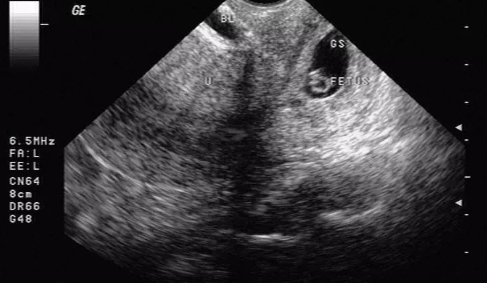

同時(shí),患者需要進(jìn)行超聲檢查,超聲檢查是目前早期診斷宮頸妊娠最直接有效的首選方法。超聲檢查時(shí)宮頸管內(nèi)見妊娠囊影像,有時(shí)可見胚胎心管搏動(dòng)。子宮體正常大小或稍大,宮腔內(nèi)無孕囊回聲;或者宮頸管內(nèi)見混合性包塊,與宮頸管肌壁間界限不清。但是宮頸妊娠主要需要與流產(chǎn)(難免流產(chǎn)、不全流產(chǎn)、先兆流產(chǎn))相鑒別。另外還需要與宮頸峽部妊娠、滋養(yǎng)細(xì)胞腫瘤、宮頸腫瘤性或炎癥性疾病相鑒別。